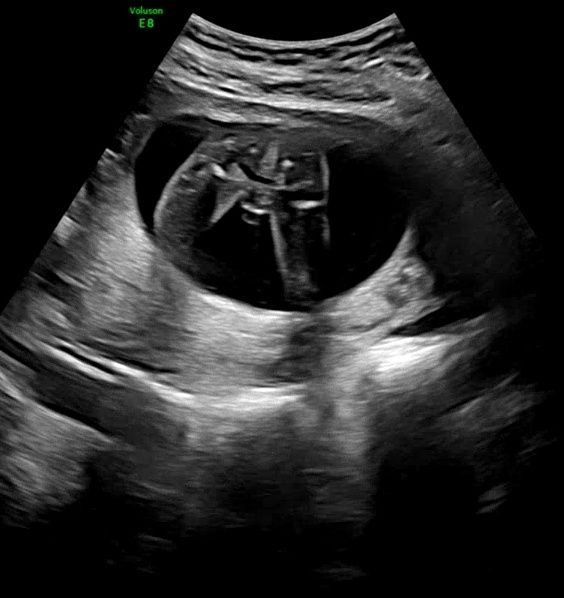

아들 맞을까요? 일란성 쌍둥이입니다

확실한거같죠?....ㅎㅎ